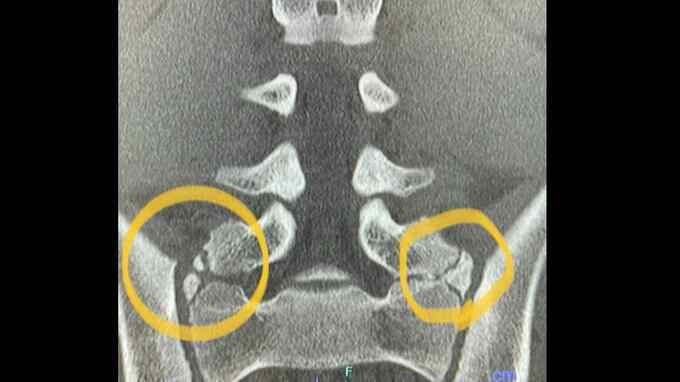

浅田匠さん「骨盤の骨折がまだ治っていないのもありますし、アップしないと体が全然動かないんですよ。睡眠時間を削ってもアップしようと、早めに来ています」

実は、浅田さんは3月に腰の骨を疲労骨折し、まだ完治していません。いまも痛みがありますが、他のメンバーには見せないようにしています。